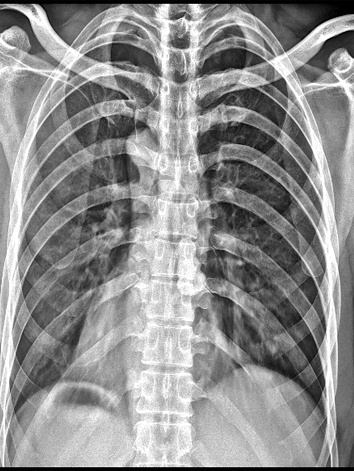

伪影在医学影像学中有多种表现形式。在X光影像中,伪影可能表现为高密度的斑点或线条,这些并不是体内真实的结构,而是由于设备或患者的因素产生的。同样,在MRI和CT等复杂设备生成的图像中,伪影也可能表现为异常的密度或信号,干扰医生的观察和判断。

产生伪影的原因有很多。一些伪影是由于设备自身的限制或故障导致的,例如设备的空间分辨率不足、图像处理算法错误等。另一些伪影则是由患者的因素引起的,例如患者在检查过程中移动、体内金属异物的存在等。

伪影的存在对医生的诊断会产生不利影响。伪影可能会掩盖患者体内真实的病变或结构,导致医生无法准确判断病情。其次,伪影可能会误导医生对病情的判断,伪影还可能影响医生对病情严重程度的评估,导致遗漏或不必要的治疗。